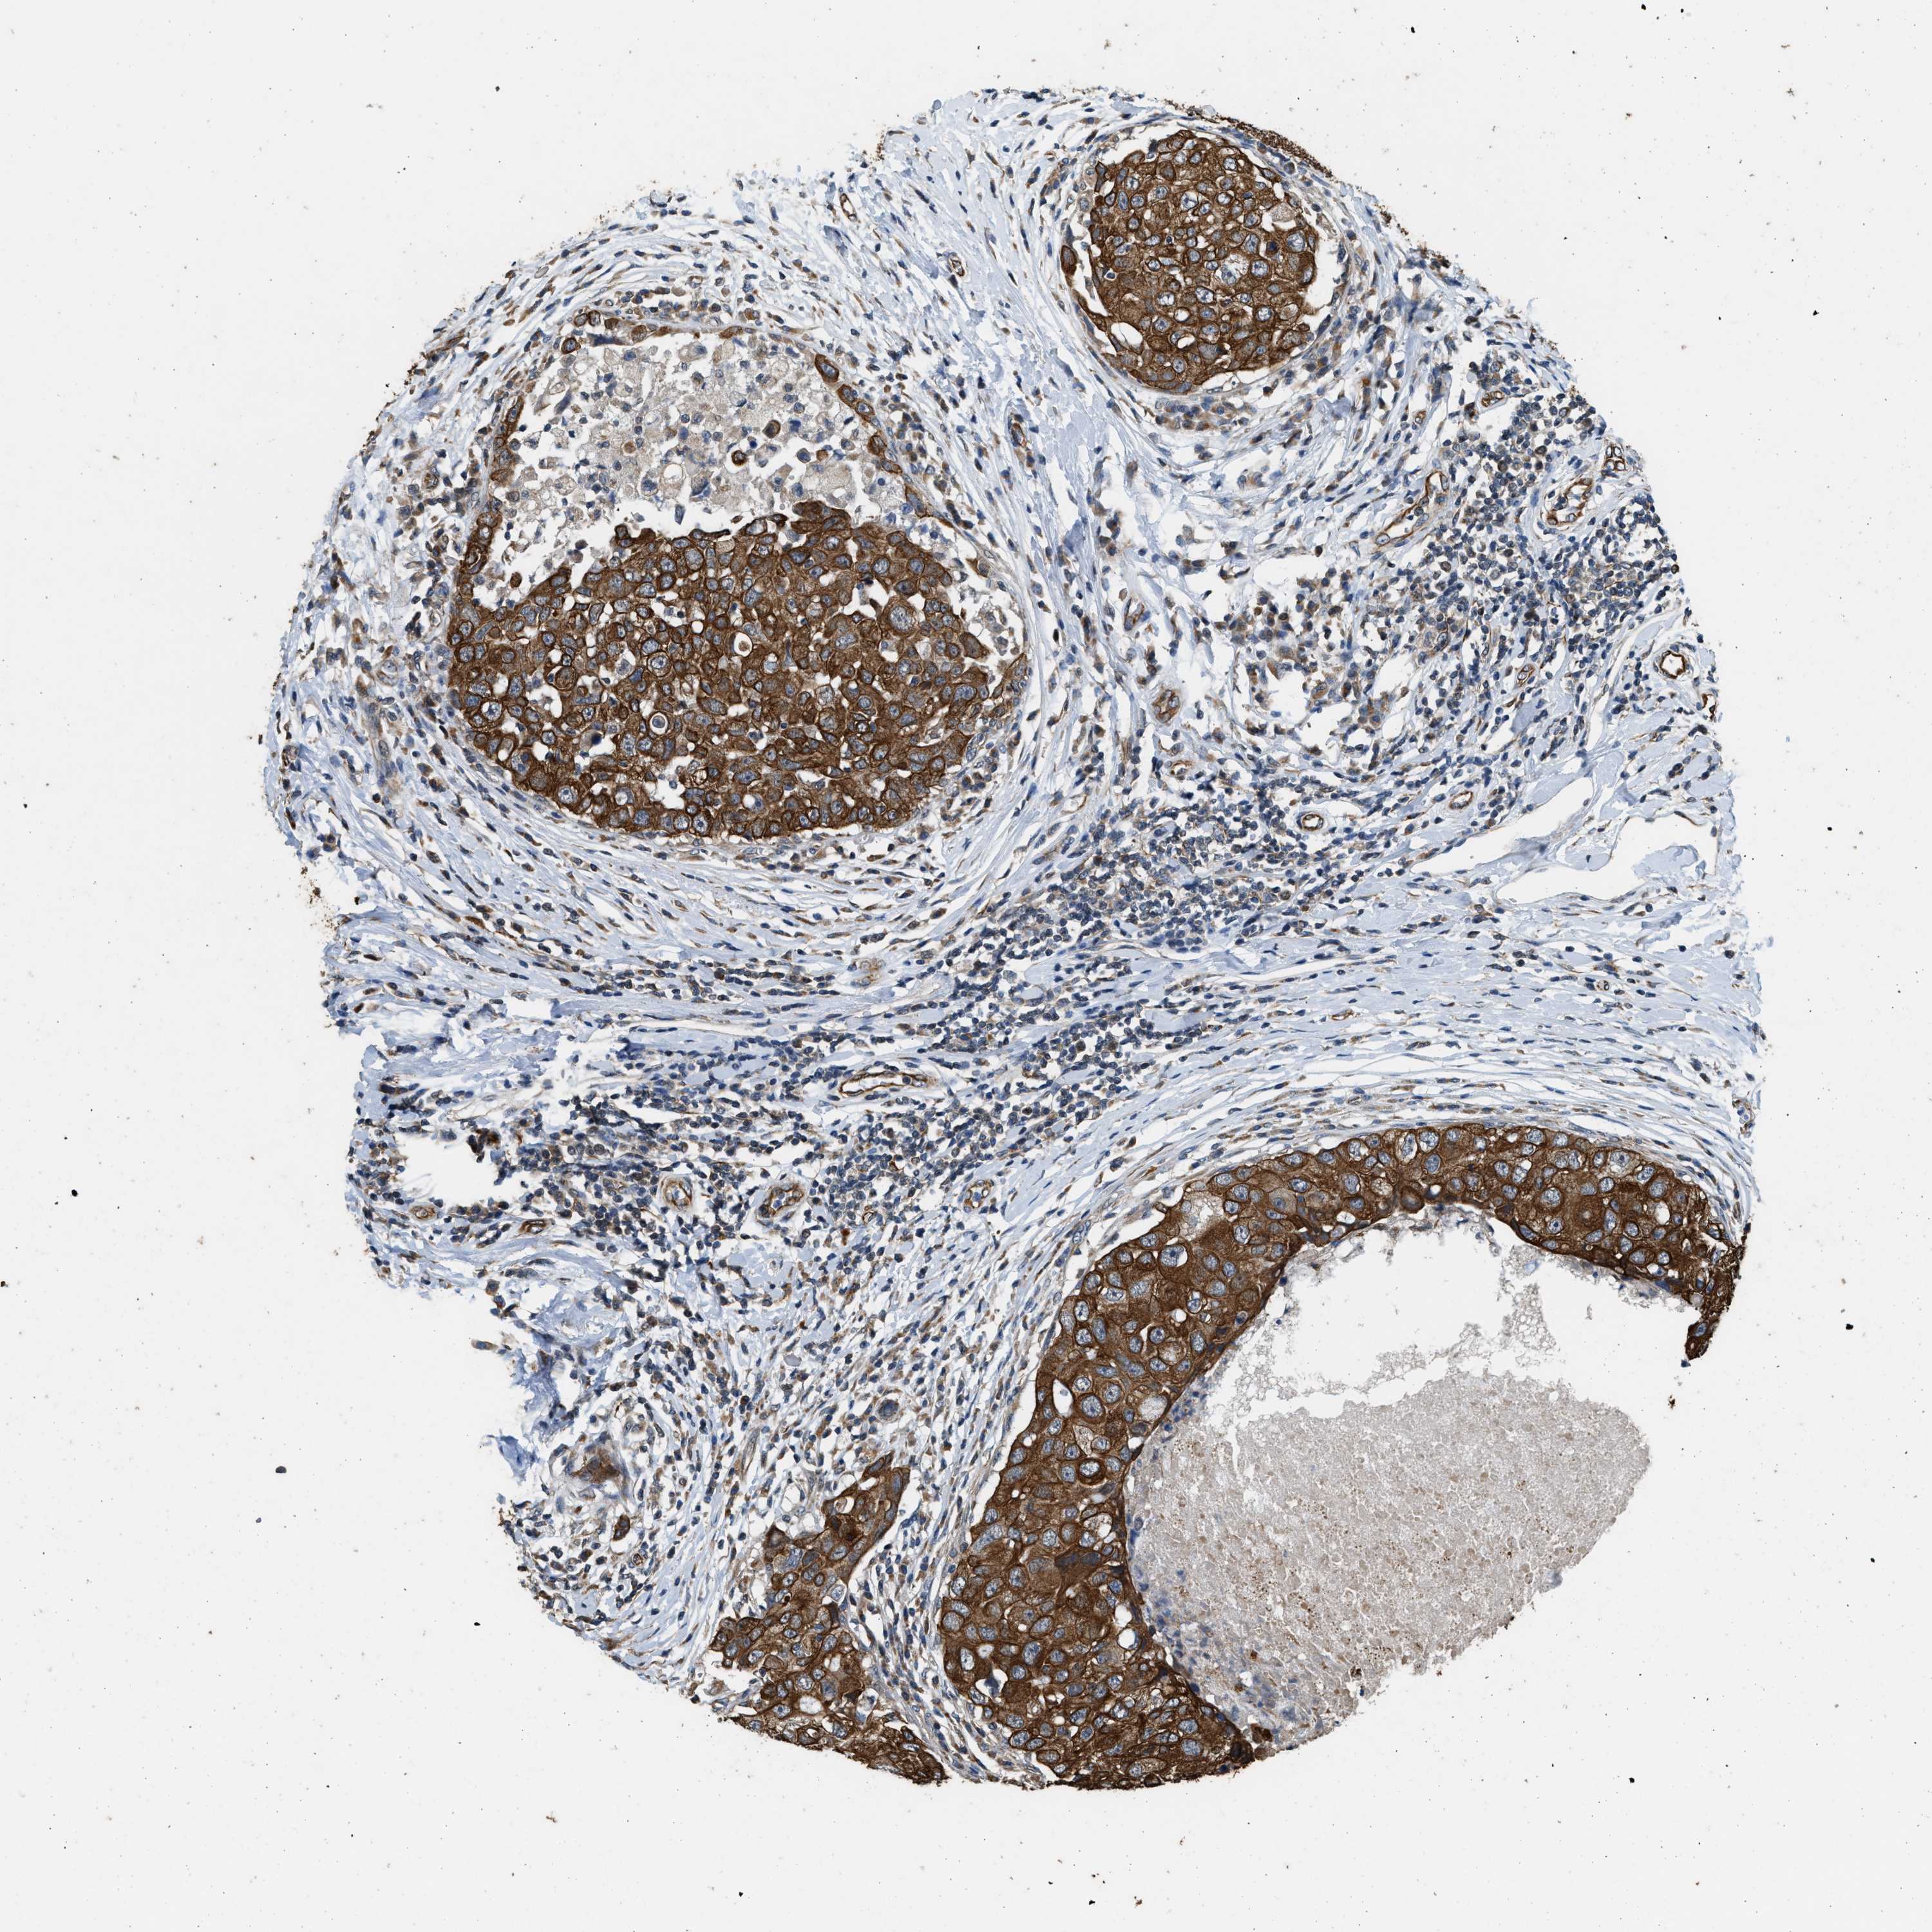

BRCA TCGA BRCA VALIDATION PROTEIN EXPRESSION

ANTIBODIES

AND

VALIDATION